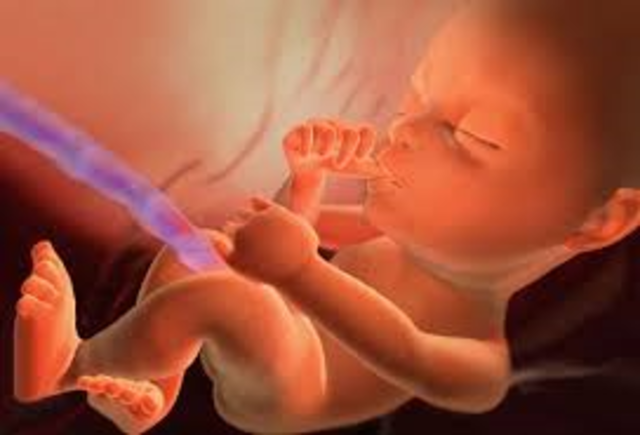

• Week 12

Week 12

Fetus' face is starting to look like a human baby. Nails start appearing. Pancreas begins to function and fetus can hiccup and suck thumb